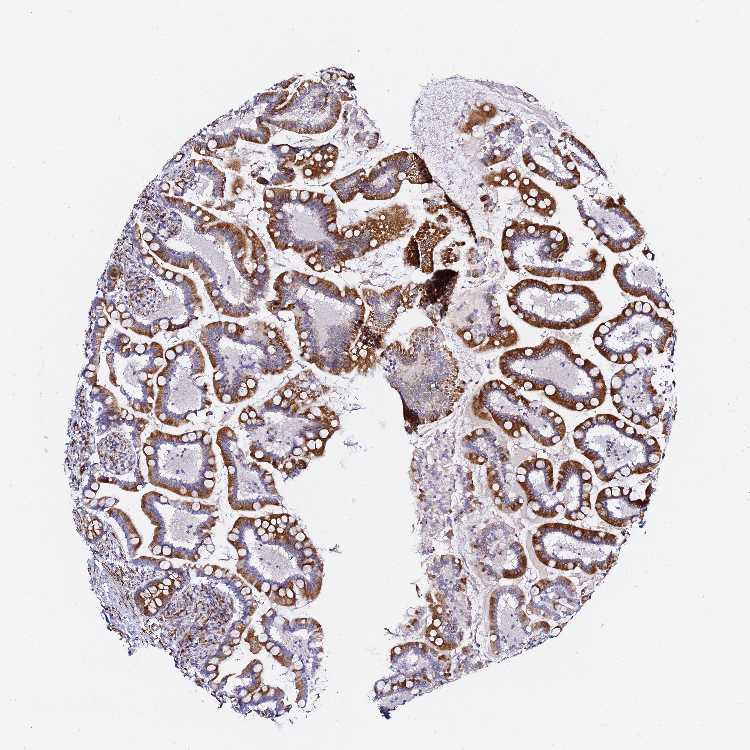

SMALL INTESTINE - Antibody stainingi

Antibody staining in the annotated cell types in the current human tissue is reported as not detected, low, medium, or high, based on conventional immunohistochemistry profiling in selected tissues. This score is based on the combination of the staining intensity and fraction of stained cells.

Each image is clickable and will lead to virtual microscopy that enables deeper exploration of all samples and also displays staining intensity scores, fraction scores and subcellular localization as well as patient and tissue information for each sample.

Antibody HPA043684Antibody HPA063394Antibody CAB046031

Glandular cells MediumMediumHigh